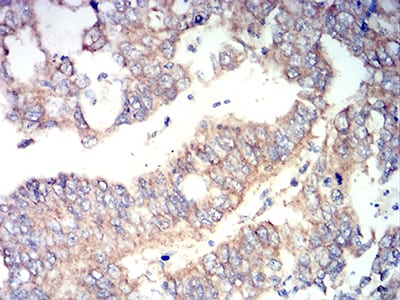

| IHC | 1/200 - 1/1000 | Human,Mouse,Rat |

These antibodies are widely used in techniques like Western blotting, immunohistochemistry (IHC), and immunofluorescence (IF) to detect RUNX3 expression levels, subcellular localization, and post-translational modifications. Researchers employ them to investigate RUNX3's role in tissue-specific gene regulation, immune cell maturation (e.g., T cells and dendritic cells), and its dual functions in cancer progression—acting as either a tumor suppressor or context-dependent oncogene. Commercially available RUNX3 antibodies are typically raised against specific epitopes in human or mouse RUNX3. with validation in knockout cell lines to ensure specificity.

In clinical research, RUNX3 antibody-based assays help correlate protein expression patterns with disease prognosis, therapeutic responses, or epigenetic silencing in tumors. They also facilitate studies on RUNX3's involvement in autoimmune disorders and inflammatory conditions. Proper antibody selection requires consideration of cross-reactivity with other RUNX family members (RUNX1/2) and species compatibility.